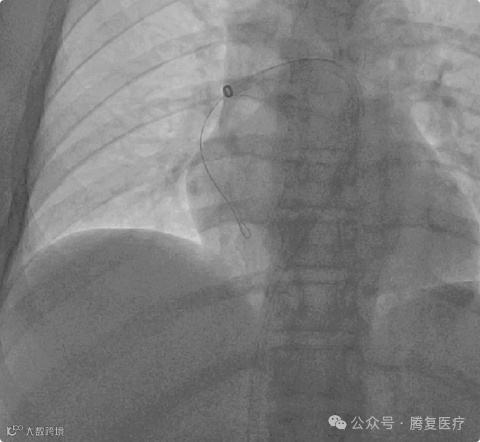

将 TF-15-18 型号的Tendvia™肺动脉⾎栓取⽀架沿导丝通过抽吸导管向前推送⾄右肺动脉⾎栓位置 ,⽀架头端穿过⾎ 栓 ,回撤输送鞘管 ,⽀架⾃动膨开 ,等待 90 秒 ,连接抽吸器并形成负压 ,回撤取栓⽀架的同时旋转开关释放负压,

取栓支架展开